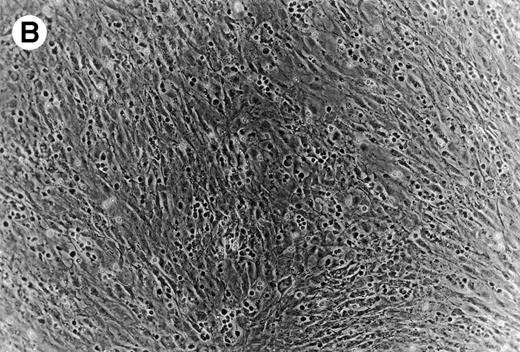

Coculture of CLL cells with the murine-marrow-stroma cell-line, M2-10B4, results in spontaneous migration of CLL cells into the stromal cell layer. This in vitro phenomenon termed pseudoemperipolesis is characterized by the dark appearance of cells that have migrated into the same focal plane as the stromal cells, whereas the more superficial, nonmigrated cells remain refractile (Fig 6).30 Time-course experiments showed that pseudoemperipolesis of CLL cells mostly occurred within the first 2 hours of coculture (Fig 7B). Titration of the input CLL cell numbers showed that concentrations above 1 × 107 cells per 24 well plate did not significantly increase the number of migrated cells (Fig 7C). A 2-hour assay with 1 × 107 input cells was found to be the optimal condition for this assay and hence was used in subsequent inhibition studies. Under these conditions, an average of 7.4% ± 3.7% (mean ± SD) of input CLL cells from 6 different patients migrated into the stromal layer. For comparison, we assessed the migration of Nalm-6 cells and found that 6.9% ± 0.5% (mean ± SE of duplicate tests) of the input cells migrated into the stromal layer under the same experimental conditions.

(A) Representative phase contrast photomicrograph of pseudoemperipolesis of CLL B cells after 2-hour culture on the heterologous murine stromal cell line, M2-10B4. Cells that had not migrated beneath the stromal cells washed off, and the stromal cell layer containing the migrated CLL cells was photographed (200x magnification). Pseudoemperipolesis is characterized by the dark appearance of lymphocytes that have migrated into the same focal plane as the stromal cells. (B) For comparison, this photomicrograph shows reduced pseudoemperipolesis after pretreatment of CLL cells with pertussis toxin.